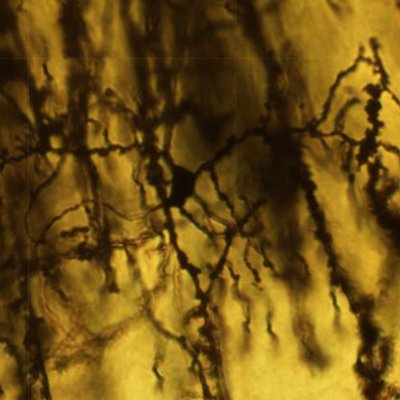

Cerebelo